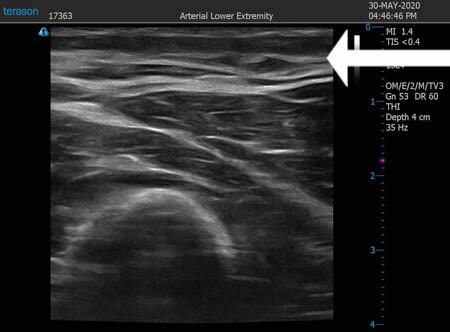

いつものように3Dタッチビュー(超音波)で

皮下脂肪層を評価してみましょう。

右ちからこぶ

↓ ↓ ↓

上の画像の部分の皮下脂肪層をつまんでみましょう。